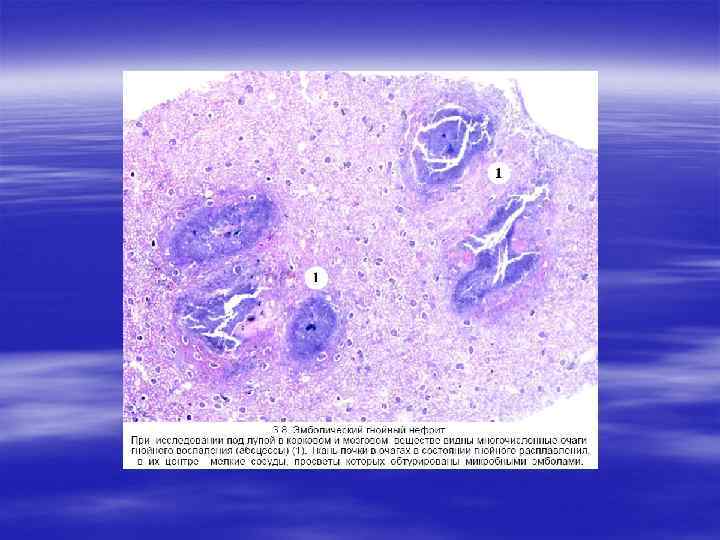

ОСТРЫЙ ПИЕЛОНЕФРИТ § Пиелонефрит — острое гнойное воспаление почек, при котором в процесс вовлекаются почечные лоханки, чашечки, интерстиций почечной паренхимы.

§ Патологическая анатомия § К осложнениям острого пиелонефрита относят: § карбункул почки, § пиелонефроз, перинефрит (переход гнойного воспаления на фиброзную капсулу почки), § паранефрит (гнойное воспаление околопочечной клетчатки)